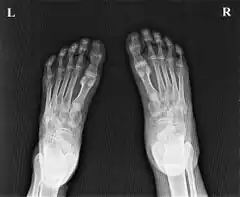

Ainhum of the left foot of a Zulu patient in Ngwelezane Hospital, KZN, South Africa.(The little toe on the opposite foot had auto-amputated several years earlier.)

Soft tissue constriction on the medial aspect of the fifth toe is the most frequently presented radiological sign in the early stages. Distal swelling of the toe is considered to be a feature of the disease. In grade III lesions osteolysis is seen in the region of the proximal interphalangeal joint with a characteristic tapering effect. Dispersal of the head of the proximal phalanx is frequently seen. Finally, after autoamputation, the base of the proximal phalanx remains. Radiological examination allows early diagnosis and staging of ainhum. Early diagnosis is crucial to prevent amputation. Doppler shows decreased blood flow in posterior tibial artery.